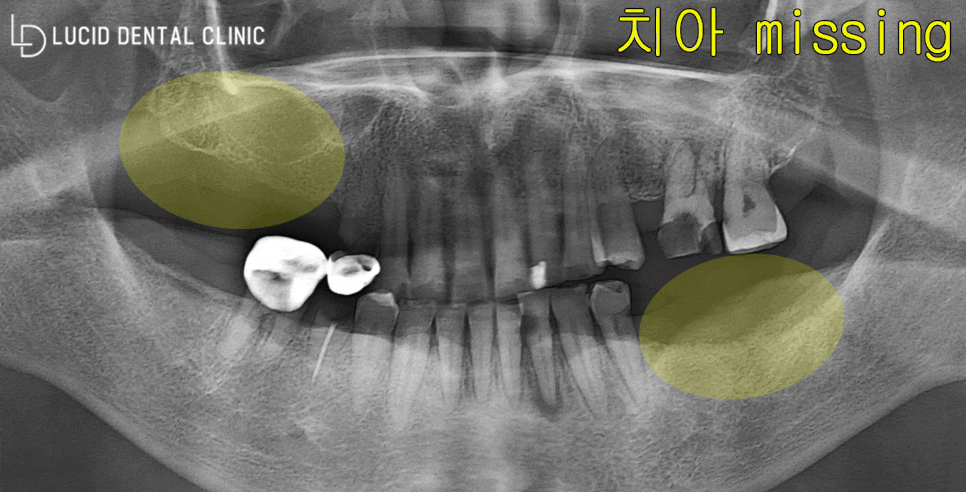

이 환자께선 다수의 치아를 소실된 채

임플란트 수술 상담을 받고 싶다며

논현동 치과 에 방문하셨는데요

디지털 엑스레이 사진을 통해 분석한 결과,

두 가지의 문제점을 발견할 수 있었습니다.

그건 바로,

잇몸 염증 및 충치 감염

발치로 인한 missing 상태

두 가지였는데요

당시 치아를 소실한 지 시간이 오래 지나,

치조골 흡수가 심하게 일어난 상태였습니다.